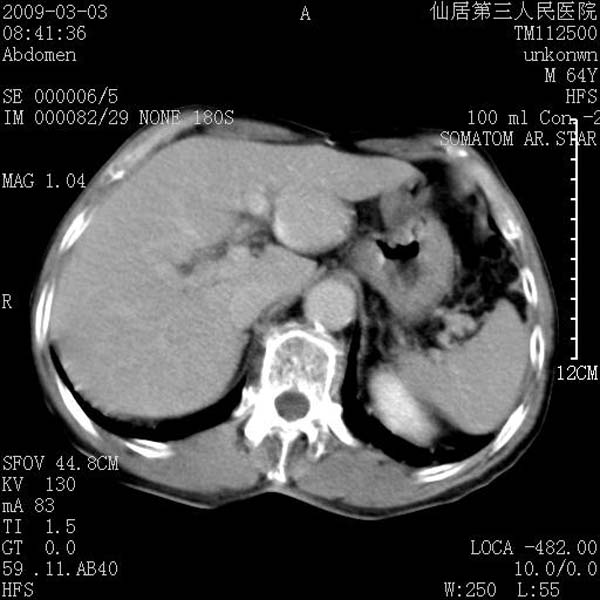

标题: CT18469:男性,64y,体检B超示肝脏低回声肿块,有胃溃疡手术 [打印本页]

患者,男性,64y,体检b超示肝脏低回声肿块,有胃溃疡手术史。

考虑----胃肠道间质瘤可能性大

从平扫及增强的特点来看,支持肝脏腺瘤并出血。

考虑胃间质瘤可能性大。

胃肠道间质瘤!

ct值呢?感觉没强化,象囊性。

考虑肝静脉韧带裂区良性占位性病变(囊肿?)。

考虑肝囊肿并出血可能性大.

考虑高密度囊肿可能性大